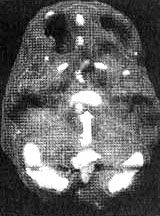

Мозг Фрэнка - болезнь Альцгеймера

Трехмерное изображение поверхности, вид сверху

Трехмерное изображение нижней поверхности

Обратите внимание на выраженное общее снижение активности, особенно в париетальных долях (см. стрелки, рис. слева) и в височных долях (см. стрелки, рис. справа).